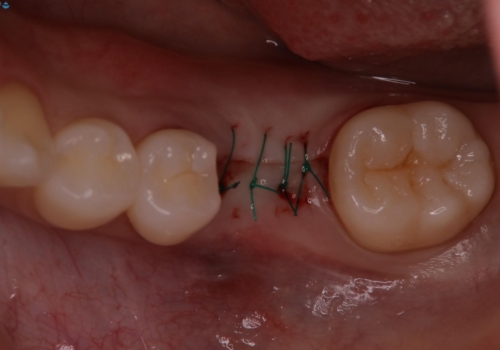

- 他院で抜歯と言われ、今後どうしたらいいのかを相談された患者様です。

抜歯を行った後は、Br、義歯、インプラント、何もしないという選択肢のメリットデメリットを説明させていただき患者様がインプラント治療を希望されたので今回治療させていただくことになりました。

歯のなかったところをインプラント治療を行うことによってまた噛める喜びを感じていただけて良かったと思っております。